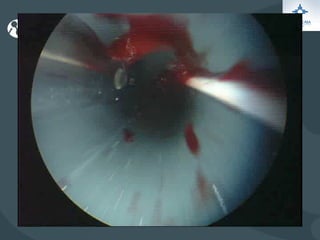

O documento discute o tratamento de urolitíase, especificamente a remoção de cálculos renais através de nefrolitotripsia. A cirurgia aberta é agora muito restrita devido aos avanços da ESWL e procedimentos endourológicos menos invasivos como ureteroscopia e cirurgia percutânea. A cirurgia laparoscópica está substituindo a cirurgia aberta como técnica menos invasiva que combina a tecnologia endourológica com a laparoscópica preservando